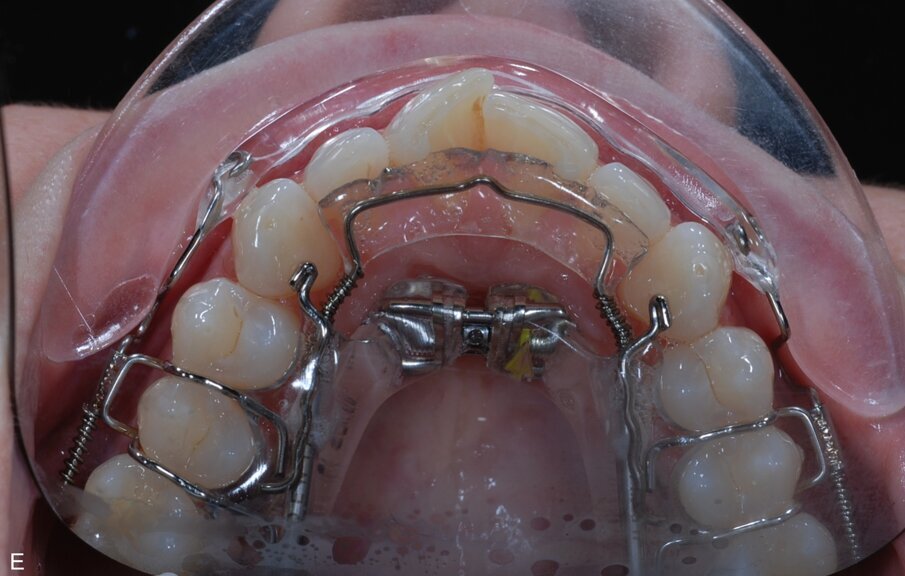

Fig. 9: ClearSmile Inman Aligner fitted

At the initial appointment, palatal anchors were placed, with interproximal reduction (IPR) and predictive proximal reduction (PPR) carried out using the guide issued from the laboratory. The patient was instructed on how to turn the expander. Aligner in situ. At the initial appointment, palatal anchors were placed, with interproximal reduction (IPR) and predictive proximal reduction (PPR) carried out using the guide issued from the laboratory. The patient was instructed on how to turn the expander. Aligner in situ. |